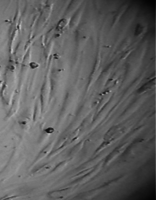

Клетки культивировали в стандартных условиях в термостате Sanyo – Incubator MIR-262 при температуре 37°С в среде МЕМ с 10% эмбриональной телячьей сыворотки в пластиковых культуральных флаконах Orange Scientific (производство Бельгии), Corning (производство США) площадью 25 и 75 кв. см. Тестирование производили в культуральных чашках Петри Sarstedt диаметром 3 см (рис. 3).

6 серия экспериментов. Образец исследуемого материала (аллогенный ГАП серии «Лиопласт»® массой 2 мг) помещали на дно культуральной чашки, после чего высевали фибробласты в стандартной концентрации.

Щелочной материал резко ухудшает прикрепление фибробластов к дну культуральных чашек (рис. 35) на всей его площади, вместе с тем прикрепившиеся клетки имеют четкие границы, нуклеолемма четко контурирует, цитоплазма гомогенная, без патологической зерностости, вакуолей и включений.

Рис. 35. Выраженная пролиферация, восстановление плотности монослоя.

Фибробласты лишь более распластаны по дну чашки, но это характерно для культуры с малой плотностью.

Вокруг образца через сутки от начала эксперимента клетки не прикрепляются (расстояние от края образца до границы 1,3±0,12 мм).

В последующие дни и до конца наблюдения плотность монослоя  в отдаленной от образца зоне нарастает даже несколько быстрее, чем в контроле, клетки сохраняют обычную для фибробластов в культуре морфологию.

Большое количество слущенных клеток в ростовой среде объясняется ухудшением прикрепления пассированных клеток, а не гибелью уже прикрепившихся (табл. 14).